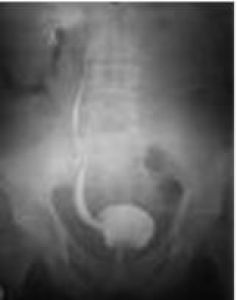

Exemple d’une vessie dite diverticulaire ou d’un reflux vésico urétéral passif, lors d’une cystographie rétrograde et mictionnelle